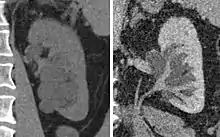

Hydronephrosis due to a kidney stone at the ureteral vesicular junction seen on CT scan

Prenatal diagnosis is possible,[7] and in fact, most cases in pediatric patients are incidentally detected by routine screening ultrasounds obtained during pregnancy.[8] However, approximately half of all prenatally identified hydronephrosis is transient, and resolves by the time the infant is born, and in another 15%, the hydronephrosis persists but is not associated with urinary tract obstruction (so-called non-refluxing, non-obstructive hydronephrosis). For these children, regression of the hydronephrosis occurs spontaneously, usually by age 3. However, in the remaining 35% of cases of prenatal hydronephrosis, a pathological condition can be identified postnatally.[9]